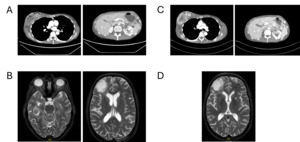

Restaging in September 2025 with contrast-enhanced CT of the thorax and abdomen and contrast-enhanced MRI of the brain demonstrated partial remission, with regression of systemic and intracranial disease and no new metastatic lesions (Figure 4). Therapeutic anticoagulation with apixaban was continued without any new thromboembolic events.

Comprehensive molecular profiling performed during ongoing treatment identified a pathogenic sBRCA2 splice-site mutation, enabling a biologically rational transition to targeted therapy with the PARP inhibitor olaparib. Importantly, olaparib was initiated after radiologic progression on chemoimmunotherapy rather than as maintenance following response, reflecting real-world treatment sequencing rather than trial-defined pathways. Under olaparib therapy, the patient again responded to treatment with regression of both systemic and intracranial disease and sustained clinical benefit with good tolerability. The intracranial response observed under PARP inhibition is clinically noteworthy, as many systemic agents demonstrate limited CNS activity, particularly in patients with a high baseline intracranial tumor burden who have already undergone whole-brain radiotherapy. Therefore, this case adds to the emerging real-world evidence supporting CNS activity and the feasibility of PARP inhibitors in BRCA-mutated TNBC.